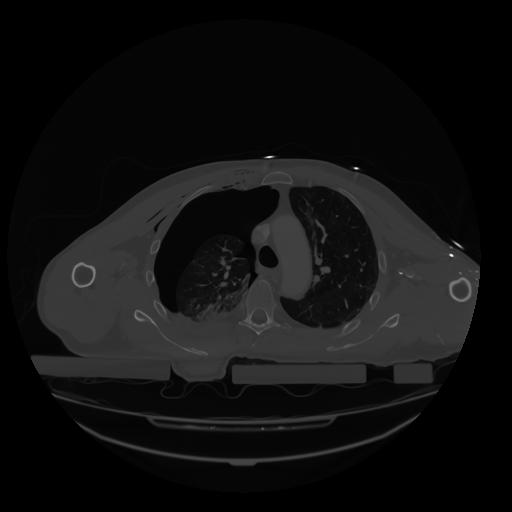

28 CUERPO,CE,Vol,2.0,CUERPO,,